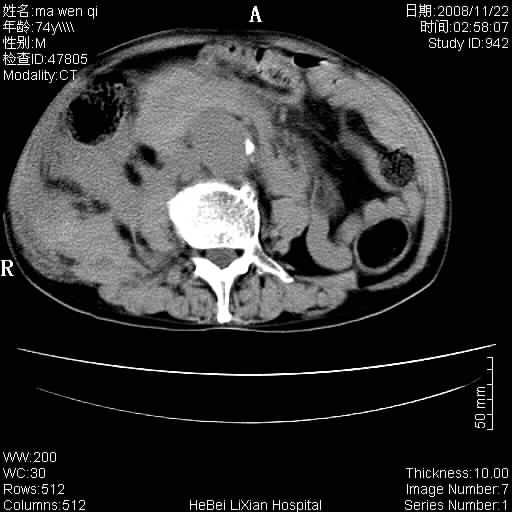

患者男 74岁.突然昏迷,休克6小时.血压70/30,头颅ct未见异常,既往体健.

补充病史,保留导尿10小时,尿袋内只有少许尿液,患者于住院后15小时后去世.

1)考虑双侧髂动脉瘤并右侧动脉瘤破裂出血,右侧腹膜后及腹腔积血。2)双侧腹股沟疝。

支持(1)双侧髂动脉瘤并右侧动脉瘤破裂出血,右侧腹膜后及腹腔积血。(2)双侧腹股沟疝。

1)考虑,腹主动脉、双侧髂动脉夹层动脉瘤破裂伴右侧腹膜后及腹腔积血。2)双侧腹股沟疝。